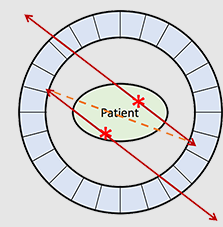

What is the relationship between each detector pair inside the ring of detectors in a PET camera?

Each detector works together with the detector opposite to it – allows it to pick up on a line of response

What is a line of response?

When the photons from an annihilation reaction are emitted, they will travel in opposite directions of one another – makes a 180-degree line almost

How does a ‘dot’ from our image translate from the reaction at the PET detectors?

The detectors create a dot on our scanned image from the point at which the 2 photons are overlapping – or where they cross each other in the ring of detectors but we still need more information to specifically determine it!

What is needed in order for the PET detectors to determine where an annihilation reaction occurred on a line of response?

Requires multiple line of responses to figure out where the intersection of where the annihilation reaction took place